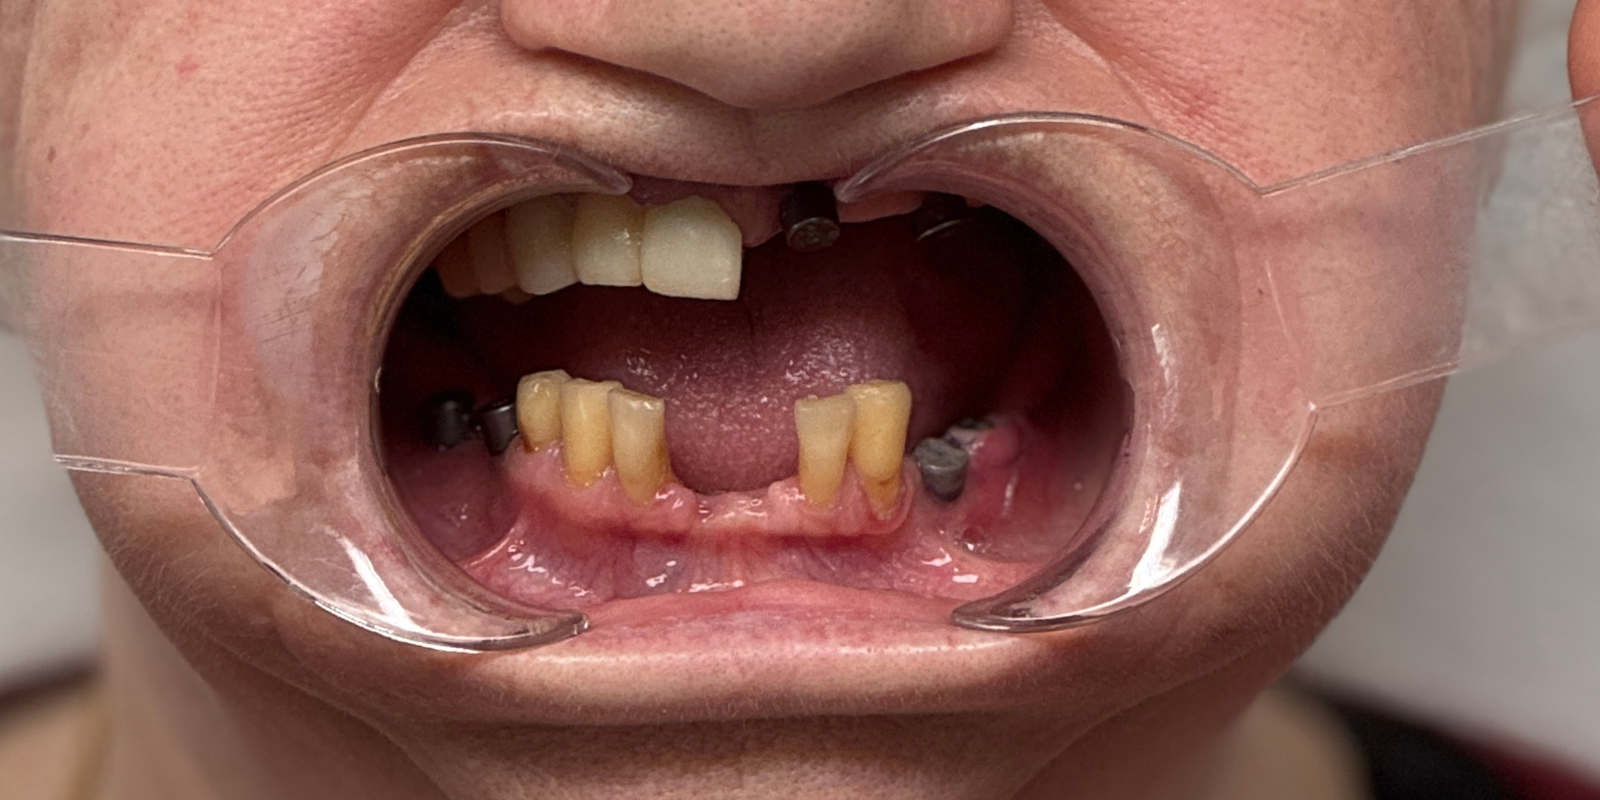

Мы провели осмотр и компьютерную томографию, чтобы оценить состояние кости и оставшихся зубов. Выяснилось: несколько зубов ещё можно сохранить, но значительную часть необходимо было удалять. На основе диагностики мы предложили комплексный план лечения.

- Удалить 4 подвижных зуба и снять старые мостовидные конструкции.